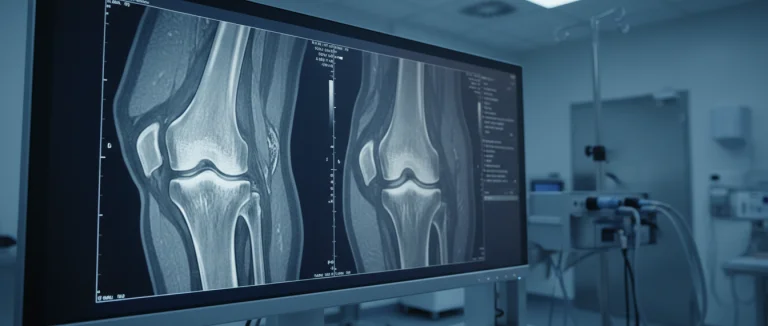

- Магнитно‑резонансная томография (MRI) – детальная визуализация хрящей, связок и нервных окончаний.

| MRI | Подозрение на внутренние повреждения, воспаления | Высокая детализация, возможность оценки нервов | Стоимость, противопоказания (металлические импланты) |